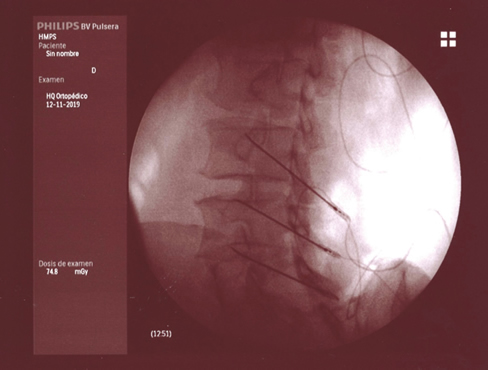

La neurotomía por radiofrecuencia del ramo medial es una técnica que está bien estandarizada a nivel cervical y lumbar, no así a nivel torácico, y que es un tratamiento que está bien establecido y estudiado con un nivel de evidencia alto (2,3,4). Por tanto, tras llegar al diagnóstico de dolor facetario el tratamiento de elección es la neurotomía por radiofrecuencia del ramo medial (Figuras 1 y 2).

Fig. 1.

Fig. 2.

La neurotomía por radiofrecuencia del ramo medial es una técnica estandarizada a nivel cervical y lumbar, con unos niveles de evidencia elevados y, por tanto, totalmente recomendable en el tratamiento del dolor facetario secundaria a la artrosis vertebral.